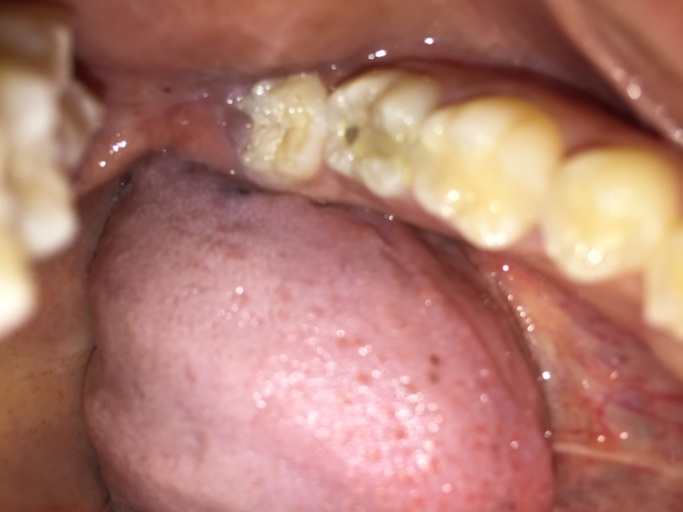

Is this a cavity in my wisdom tooth?

Hi, I am 31 and have observed a dark spot on my lower wisdom tooth (the tooth behind the one with the large silver filling on the picture). All my wisdom teeth have erupted quite good, but short after eruption I had small cavities which were filled with white fillings - that was about 12 years back. Now I see this dark spot which I think might be a new cavity besides the old filling or maybe the old white filling has fallen out. I have no pain from the tooth. I take good care of my teeth and have not had any new cavities for more than 10 years, but I have several fillings from my teenage years and some of those have been refilled over the last five year. Is it a new cavity? Will it be possible to repair my wisdom tooth with a new filling?

It is possible that your resin restoration is stained or may have come out and the underlying tooth structure, dentin, is a darker shade than the harder enamel covering the surface.  Continue with good oral hygiene habits, brushing twice daily and flossing at least once.  Limit high sugar and sticky foods until you see your dentist.  It is best to be proactive and take care of a small cavity when it is diagnosed.  Not only is the procedure less involved, but is usually less costly as well.  Resin restorations usually last 5-10 years, so it may be time to have it replaced.